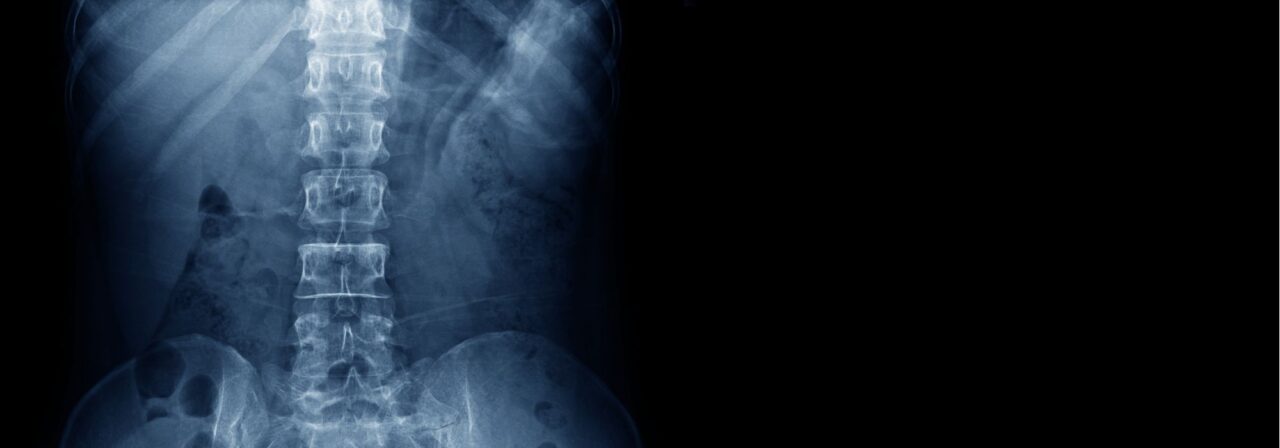

The Rothman Orthopaedic Institute’s spine team is known nationwide for its innovative and exemplary spinal treatments. Our specialists perform thousands of spine surgeries each year in the greater Philadelphia metropolitan area alone. These helpful spinal procedures treat problems resulting from degeneration of the cervical and lumbar discs, herniated discs, spinal stenosis, spinal deformity, tumors, trauma, and instability.

- Herniated Lumbar Disc

- Low Back Pain (Lumbar)